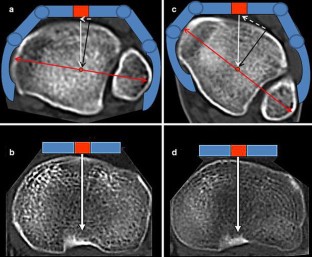

Fig. 1

Fig. 2

Fig. 3

Fig. 4

Fig. 5